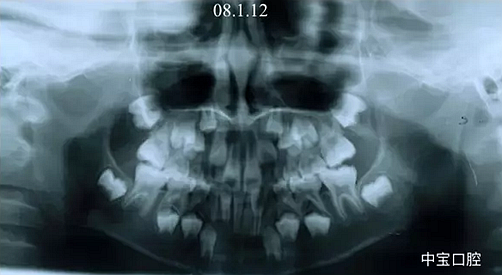

有一個七歲的小女孩,在替牙時媽媽發(fā)現(xiàn)孩子新長的牙不整齊,有一顆長到里面了,上下頜中線也不對稱,很著急就來到門診看牙。

經(jīng)過我臨床檢查和X線的診斷,決定早期干預(yù),每三個月定期復(fù)診檢查一次,并拔掉了幾個乳牙和四個恒牙,正畸專業(yè)叫序列拔牙。

這個故事告訴我們,只有家長早點把孩子帶給正畸醫(yī)生檢查,才能早期發(fā)現(xiàn)早期治療。起到了事半功倍的效果。矯正以后還不容易復(fù)發(fā),因為從08年的初診到11年戴矯正器這三年多的時間里,孩子的牙齒是自己長好的。